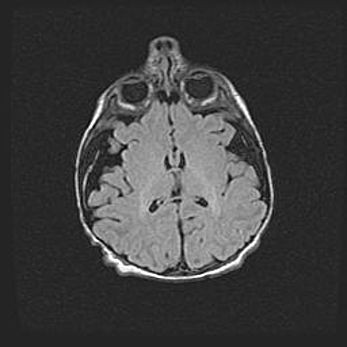

Наружная гидроцефалия с возможной атрофией височных областей.

Возраст: 28 дней

Вес: 3670 г

Пол: мужской

Окружность головы: 38 см

Срок гестации: 40 недель

Гидроцефалия головного мозга у новорожденных – это заболевание, которое характеризуется скоплением избыточного количества спинномозговой жидкости в желудочковой системе головного мозга в результате затруднения её перемещения от места выработки к месту поглощения в кровеносную систему или вследствие нарушения абсорбции. При открытой наружной форме гидроцефалии у новорожденных расширяются и переполняются субарахноидные пространства.

При нормотензивных  формах,  которые,  как  правило,  являются  следствием  перенесенных ишемических  повреждений  паренхимы  мозга,  возможно  сочетание микроцефалии  с нормотензивной гидроцефалией. В основе данных изменений лежит атрофия больших полушарий с преимущественной  локализацией  в  лобно-височных  областях.